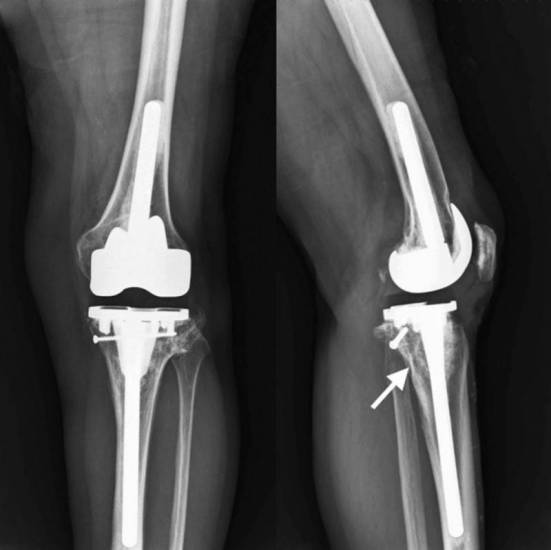

- бесцементный. Имплантаты имеют специальную текстурированную, пористую поверхность, через которую костная масса свободно прорастает во внутреннюю полость эндопротеза. Винты и штифты стабилизируют соединение, пока не произошло врастание. При установке приспособления требуется более длительный период восстановления. Не применяются для пациентов с остеопорозом, поскольку врастающая кость должна быть в хорошем состоянии.